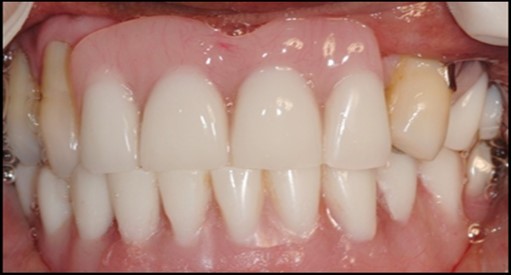

A 63 year old male patient came to our Aesthetics Dental Clinic ,Athens, Greece with the chief complaint of loose fitting lower denture with difficulty in mastication and speech. On examination, patient had resorbed alveolar ridge which lead to inadequate retention of the lower denture prosthesis and patient is known to be a previous denture wearer for past 1 year. The Orthopantomograph findings showed the presence of sufficient bone height and width (Figure 1), with dense cortical bone surrounded by dense trabecular bone. Thus implant supported overdenture was planned with two implants along with independent ball type attachments.

Figure 1.First Visit Pre-operative radiograph

First Visit Pre-operative radiograph